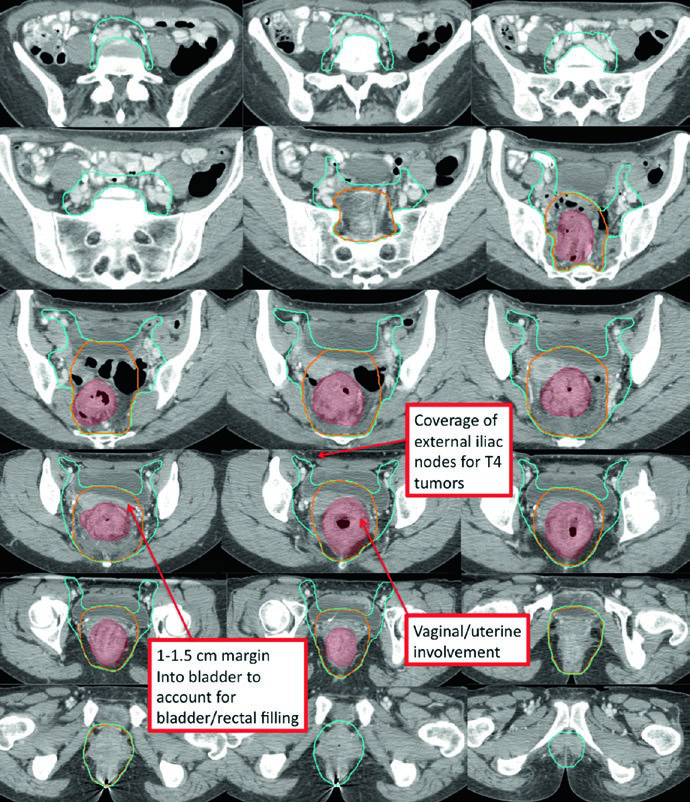

The standard-risk CTV (CTV-SR) covers the entire CTV-HR, mesorectum, and bilateral internal iliac lymph nodes. For T4 tumors with anterior organ involvement (bladder, cervix, prostate), the bilateral external iliac and obturator nodes must be included. If the primary tumor extends into the anal canal, bilateral external iliac and inguinal nodes are added to CTV-SR.

T4 disease with anterior organ invasion significantly expands the treatment volume. The CTV-SR must cover the external iliac nodal region, and the anterior border of lateral fields needs adjustment to at least 1 cm anterior to the pubic symphysis.

Low-lying rectal tumors involving the anal canal present a distinct challenge. Bilateral inguinal coverage becomes mandatory, and IMRT is typically necessary to achieve adequate conformality covering the external iliac and inguinal nodes bilaterally. The overlap with anal cancer target delineation is significant, since both share many of the same nodal drainage pathways.

The RTOG anorectal contouring atlas defines three elective CTVs. CTV-A encompasses the perirectal, presacral, and internal iliac regions and should be covered in all rectal cancer patients. CTV-B includes the external iliac nodes, covered only for T4 tumors invading adjacent organs or extending into the anal canal. CTV-C covers the inguinal region, only for tumors extending into the anal canal.

| Lower pelvis | Inferior: 2 cm below gross disease, including the entire mesorectum down to the pelvic floor. Lateral: a few mm beyond the levator muscles unless tumor extends into the ischiorectal fossa. 1-2 cm margin around T4 invasion areas |

| Mid-pelvis | Includes rectum, mesorectum, internal iliac region, and 1 cm margin into the bladder. Posterolateral to pelvic sidewall muscles or bone. Anterior: at least 1 cm into the posterior bladder. 7-8 mm margin around internal iliac vessels |

| Upper pelvis | Superior (perirectal): rectosigmoid junction or at least 2 cm cephalad to gross disease. Superior (nodal): bifurcation of common iliac vessels, approximately at the sacral promontory. 7-8 mm margin around internal iliac vessels, at least 1 cm anteriorly |